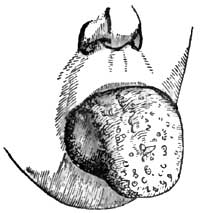

| 15. | HYPERTROPHY OF TONGUE (HARRIS), BEFORE OPERATION AND AFTER |